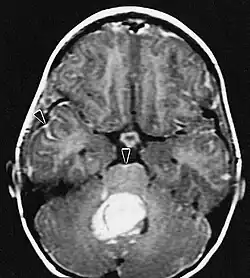

A ressonância magnética geralmente mostra uma lesão maciça com realce de contraste envolvendo o cerebelo. Como mencionado acima, o meduloblastoma tem alta propensão a infiltrar localmente as leptomeninges, bem como a se espalhar pelo espaço subaracnóideo, envolvendo os ventrículos, a convexidade cerebral e as superfícies leptomeníngeas da coluna. Consequentemente, é necessário trazer todo o eixo cranioespinhal em ressonância.

As metástases cerebrais são as neoplasias intracranianas mais comuns em adultos, sendo dez vezes mais comuns que os tumores cerebrais primários. Eles pisam em 20 até 40 por cento dos adultos com câncer e estão associados principalmente ao câncer de pulmão e mama e melanoma . Essas lesões resultam da disseminação de células cancerígenas pela corrente sanguínea e ocorrem mais comumente na junção da substância cinzenta e branca, onde a seção transversal dos vasos sanguíneos se altera, aprisionando embolias de células tumorais . 80 por cento das lesões ocorrem nos hemisférios cerebrais, 15 por cento no cerebelo e 5 por cento no tronco cerebral. Cerca de 80 por cento dos pacientes têm história de câncer sistêmico e 70 por cento têm múltiplas metástases cerebrais.

Avanços significativos foram feitos recentemente no diagnóstico e tratamento dessas lesões, resultando em melhora da sobrevida e controle dos sintomas. O início dos sinais e sintomas é semelhante ao de outras lesões maciças no cérebro. O método diagnóstico de escolha é a ressonância magnética com meio de contraste.